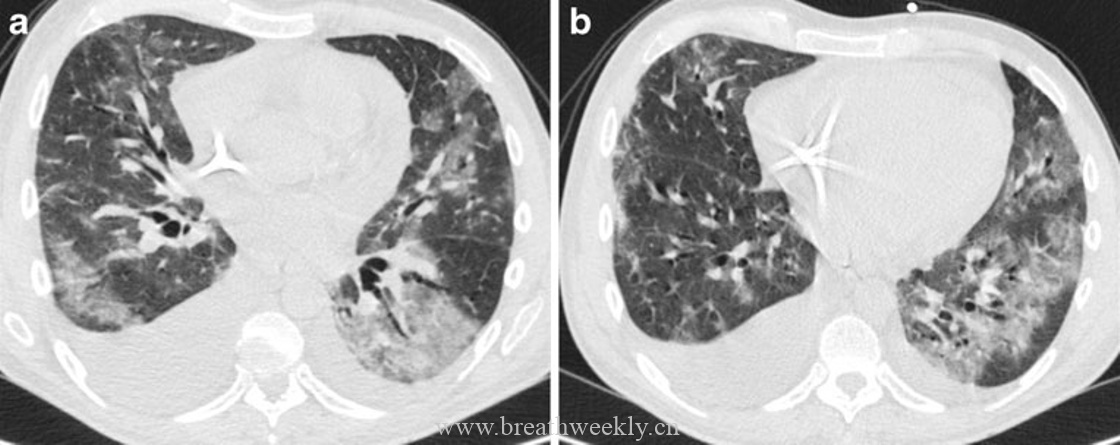

病例5:放射性肺炎

临床资料:71岁男性,小细胞肺癌放疗后出现发热、咳嗽。

影像表现:CT显示放疗区域内斑片状铺路石征。

病理对照:气腔内渗出物填充,间质增厚,不规则纤维化。

病例6:外源性脂质性肺炎

临床资料:54岁男性,进行性呼吸困难。

影像表现:CT显示右中下叶铺路石征。

病理对照:肺泡内脂质颗粒,部分被巨噬细胞吞噬,形成脂质肉芽肿。

放射性肺炎局限于放疗野内。急性期(放疗后4-12周)组织学表现为弥漫肺泡损伤,肺泡管和呼吸性细支气管内透明膜形成,肺泡内蛋白样渗出物填充。这对应CT上的磨玻璃影。网状影由毛细血管充血和间质水肿引起。

癌性淋巴管炎是肿瘤向肺淋巴系统弥漫播散的转移性肺疾病。肿瘤细胞播散至肺淋巴系统和淋巴周围间质组织时,CT显示间质增厚。